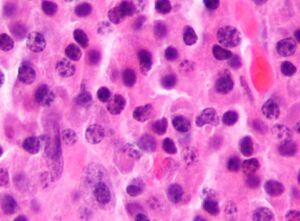

| Micrograph of a plasmacytoma. H&E stain | |

Bone marrow aspirate showing the histologic correlate of multiple myeloma under the microscope. H&E stain.